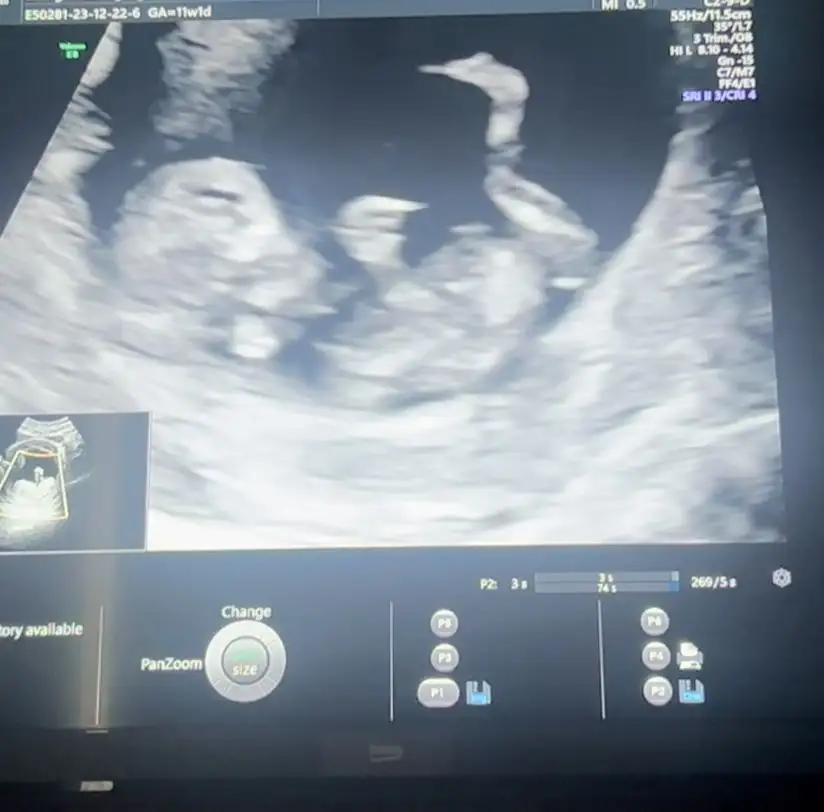

Hayırlı olsun canımKızlar selam bende bugün gittim doktora kontrolüm vardı herşey yolunda çok şükür 11+1 dedi cinsiyet tahmin etti ama söylemicem daha dedi ikili test yapıldı bugün sonucum 1 hafta sonra çıkcakmış benim ölçümlerime göre bir sorun yok herşey normal gözüküyor dedi bi sıkıntı çıkacağını düşünmüyorum dedi ayrıca progestan fitili günde 4 ten 1 e düşürdü progestan ampul ve estroferm mi bıraktırdı folik asidide bıraktırdı vitamin ve demir hapı yazdı Allahıma şükürler olsun bu günleri nasip etti öyle güzeldi ki resmen zıplıyordu ultrasonda şok olduk kıpır kıpır durmuyorRabbim herkese nasip etsin bu duyuguyu isteyen herkes için dua ediyorum Allahım herkesin gönlüne göre nasip etsin

Merhaba canım..maşallah sağlıkla gelsin..bizimki hareket etmiyordu dedim babası gibi tembel mi bu neMerhaba kızlar benimde dün doktor randevum vardı , 11+2 günlük ultrasonla da uyumluydu , embriyoma transfer öncesi genetik test yaptırdığımız için sadece ense kalınlığı ve burun kemiğine bakıldı hiçbir sorun yoktu çok şükür , cinsiyette büyük ihtimalle erkek dedi bacak arasında bir çıkıntı vardı ama 2 haftaya daha net belli olurmuş.